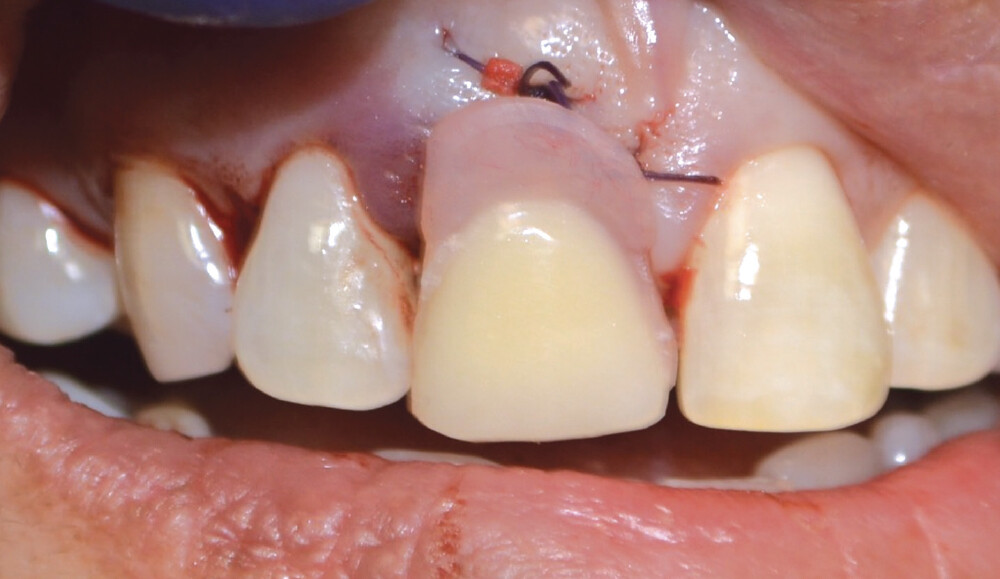

After the tooth was extracted, the site was thoroughly curetted. A pilot drill was used to begin the osteotomy, which was enlarged to the correct size for the implant. Prior to placing the implant, OsteoGen strip alloplast was re-hydrated with sterile saline and then placed in the socket against the wall adjacent to the gap. Hahn™ Tapered Implant (Glidewell Direct; Irvine, Calif.) was driven into place, and the graft material filled the gap. A healing abutment was placed and the site sutured with a Reli® REDISORB® PRO PGA 4-0 suture.